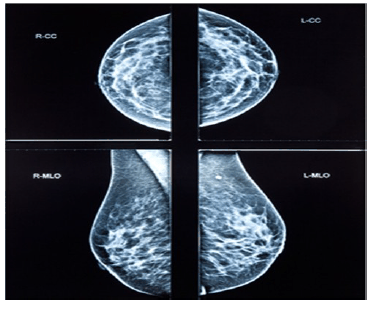

Uma paciente de 32 anos de idade, preocupada pelo fato de sua tia materna ter falecido por um câncer de mama aos 58 anos de idade compareceu à consulta e o médico solicitou uma mamografia digital. A imagem do exame realizado é apresentada a seguir.

O laudo do exame revela mamas densas com ausência de nódulos, apresentando linfonodos no respectivo prolongamento axilar, com pequenos cistos distribuídos em ambas as mamas com até 3 mm de diâmetro em sua dimensão máxima. O radiologista atribuiu a classificação BIRADS escore 2 para ambas as mamas.